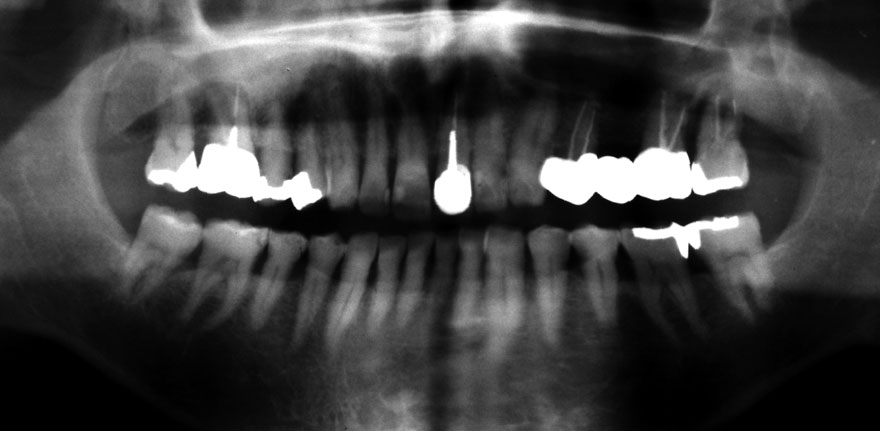

初診時 38歳 男性 平均歯槽骨喪失量:6.520mm

25年後 63歳

平均歯槽骨喪失量:8.57mm

25年間喪失量:-2.05mm

年間喪失速度:-0.08mm

(ケア頻度:1.38ヵ月ごと)